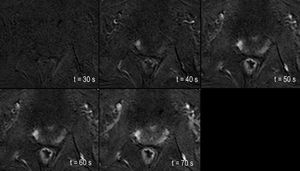

Prostate perfusion-weighted imaging (PWI)

Detection of an early contrast uptake on the DCE-MRI T1-w sequence (here with subtraction) can dramatically help radiologists finding the cancer within the gland.